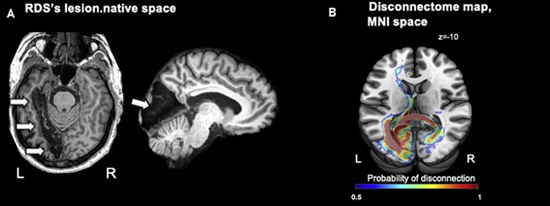

(A) IRM montrant les lésions cérébrales post-AVC de RDS (flèches) et (B) Cartographie IRM des déconnexions cérébrales entre les deux hémisphères. Crédits : Katarzyna Siuda-Krzywicka et al. 2019

Avant son AVC, RDS percevait et nommait les couleurs normalement. Après son AVC, une IRM a révélé une lésion dans la région gauche de son cerveau. Cette lésion aurait apparemment coupé la mémoire des noms des couleurs de RDS, de sa perception visuelle des couleurs et de son système de langage. Cependant, RDS pouvait toujours regrouper la plupart des couleurs, même impossibles à nommer, dans des catégories telles que sombre ou clair ou comme un mélange d’autres couleurs.